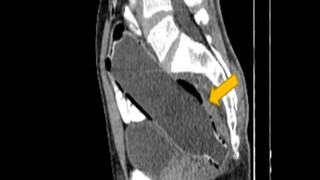

ইরানের সারির বাসিন্দা ওই ব্যক্তি নিজের পায়ুপথে একটি জলের বোতল ঢুকিয়েছিলেন মলাশয়ে। প্রায় সাড়ে সাত ইঞ্চি লম্বা এক জলের বোতল উল্টো করে ঢুকিয়েছিলেন নিজের মলাশয়ে। কিন্তু পরে আর কোনও ভাবেই সেটি বের করতে পারেননি। স্ত্রীর ভয়ে গোটা বিষয়টি মুখ ফুটে জানাতেও পারেননি। ক্রমশ খাওয়াদাওয়া বন্ধ হয়ে যায়, শুরু হয় তীব্র পেটে ব্যথা। মলত্যাগ করাও অসম্ভব হয়ে দাঁড়ায়। কোষ্ঠকাঠিন্যের সমস্যা ভেবে হাসপাতালে ভর্তি হলে সেখানে সিটি স্ক্যান করার পরেই গোটা বিষয়টি সাফ হয়। অস্ত্রোপচারের মাধ্যমে বের করা হয় সেই আস্ত বোতল।

বিজ্ঞান বিষয়ক পত্রিকা ক্লিনিক্যাল কেস রিপোর্টস জার্নালে চিকিৎসকরা জানিয়েছেন, রিপোর্ট পেয়েই তড়িঘড়ি অস্ত্রোপচারের মাধ্যমে বোতলটি বার করেন তাঁরা। কিন্তু কেন খামোখা নিজের পায়ু দিয়ে আস্ত বোতল ঢোকাতে গেলেন? সেই বিষয়ে অবশ্য নিশ্চিত নন চিকিৎসকরা। অনেকেই মনে করছেন যৌন অতৃপ্তি থেকে এমনটা করে থাকতে পারেন। চিকিৎসকেরা জানিয়েছেন, ওই ব্যক্তির মানসিক অবসাদও রয়েছে। অস্ত্রোপচারের তিন দিন পরে তাঁকে হাসপাতাল থেকে ছেড়ে দেওয়া হলেও বর্তমানে মনোবিদের তত্ত্বাবধানে রয়েছেন তিনি।